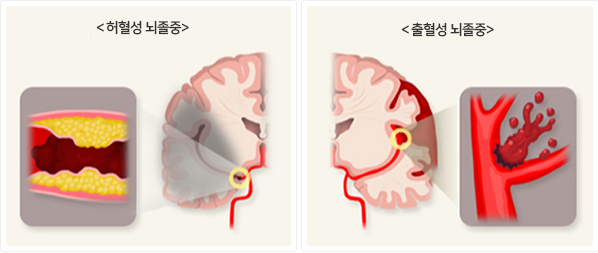

경동맥에 의한 뇌졸중은 경동맥(목에 위치한 주요 동맥)의 혈류 장애로 인해 뇌로 가는 혈액 공급이 차단되거나 감소하여 발생하는 뇌졸중입니다. 경동맥은 뇌로 혈액을 공급하는 중요한 역할을 하는데, 경동맥에 문제가 생기면 뇌로의 혈액 공급이 줄어들어 뇌졸중을 초래할 수 있습니다. 이 질환은 주로 경동맥 협착(좁아짐)이나 혈전(혈액 응고)이 원인이 됩니다.

경동맥에 의한 뇌졸중은 경동맥(목에 위치한 중요한 혈관)에서 발생하는 혈류 장애가 뇌로 가는 혈액 공급에 영향을 미쳐 뇌졸중을 초래하는 질환을 의미합니다. 경동맥은 뇌로 산소와 영양분을 공급하는 중요한 혈관으로, 이 혈관에 문제가 생기면 뇌의 일부에 충분한 혈액이 공급되지 않게 되어 뇌졸중이 발생할 수 있습니다.

주요 원인으로는 경동맥 협착(좁아짐)이나 혈전(혈액 응고)이 있으며, 이로 인해 경동맥 내의 혈류가 제한되어 뇌로의 산소 공급이 부족해지게 됩니다. 혈류가 차단되면 뇌세포가 손상되고, 이는 일시적 뇌졸중(TIA, 일과성 뇌허혈) 또는 완전한 뇌졸중(CVA, 뇌경색 등)으로 발전할 수 있습니다.